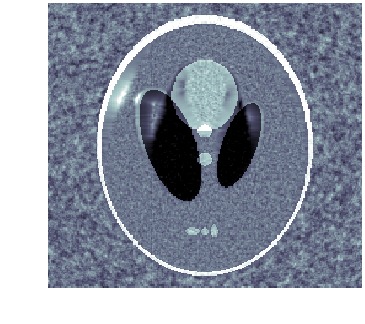

When template has correct topology and intensity levels, then \acLDDMM-based indirect registration with geometric group action is remarkably stable as shown in [9]. Using a geometric group action, however, makes it impossible to create or remove intensity, e.g., it is not possible to start out from a template with a single isolated structure and deform it to a image with two isolated structures. This severely limits the usefulness of \acLDDMM-based indirect registration, e.g., spatiotemporal images (moves) are likely to involve changes in both geometry (objects appear or disappear) and intensity. See fig. 1 for an example of how wrong intensity influences the registration.

As noted in [9], one approach is to replace the geometric group action with one that alters intensities, e.g., a mass preserving group action. Another is to keep the geometric group action, but replace \acLDDMM with a framework for diffeomorphic deformations that acts on both geometry and intensities, e.g., metamorphosis. This latter approach is the essence of metamorphosis-based indirect registration.

We clearly see that metamorphosis based indirect registration can handle a template with wrong intensities. As a comparison, see fig. 1(c) for the corresponding \acLDDMM based indirect registration using the same template and data. Furthermore, the different trajectories also provides easy visual interpretation of the influence of geometric and intensity deformations.